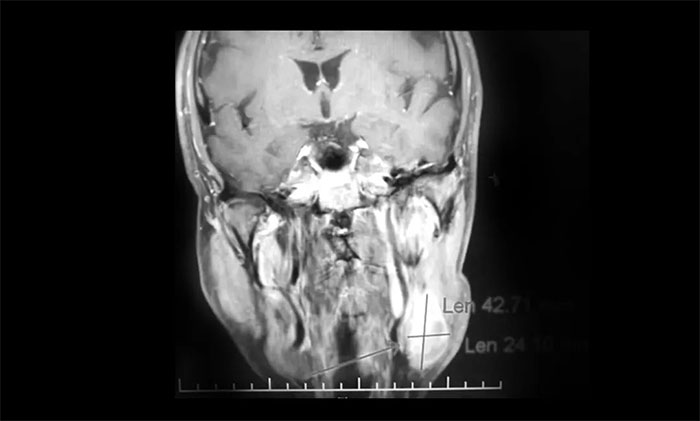

一位64岁男性患者,因“左颈部淋巴结肿大伴鼻出血半月”在外院行鼻咽镜活检病理结合影像学检查,提示鼻咽癌可能。为寻求进一步治疗近期来到我院。查MRI:左侧鼻咽部实性占位性病变,考虑恶性肿瘤,侵及左侧咽旁间隙;左侧下颌腺区及颈部淋巴结异常肿大(转移可能)。

▲ 入院MRI影像